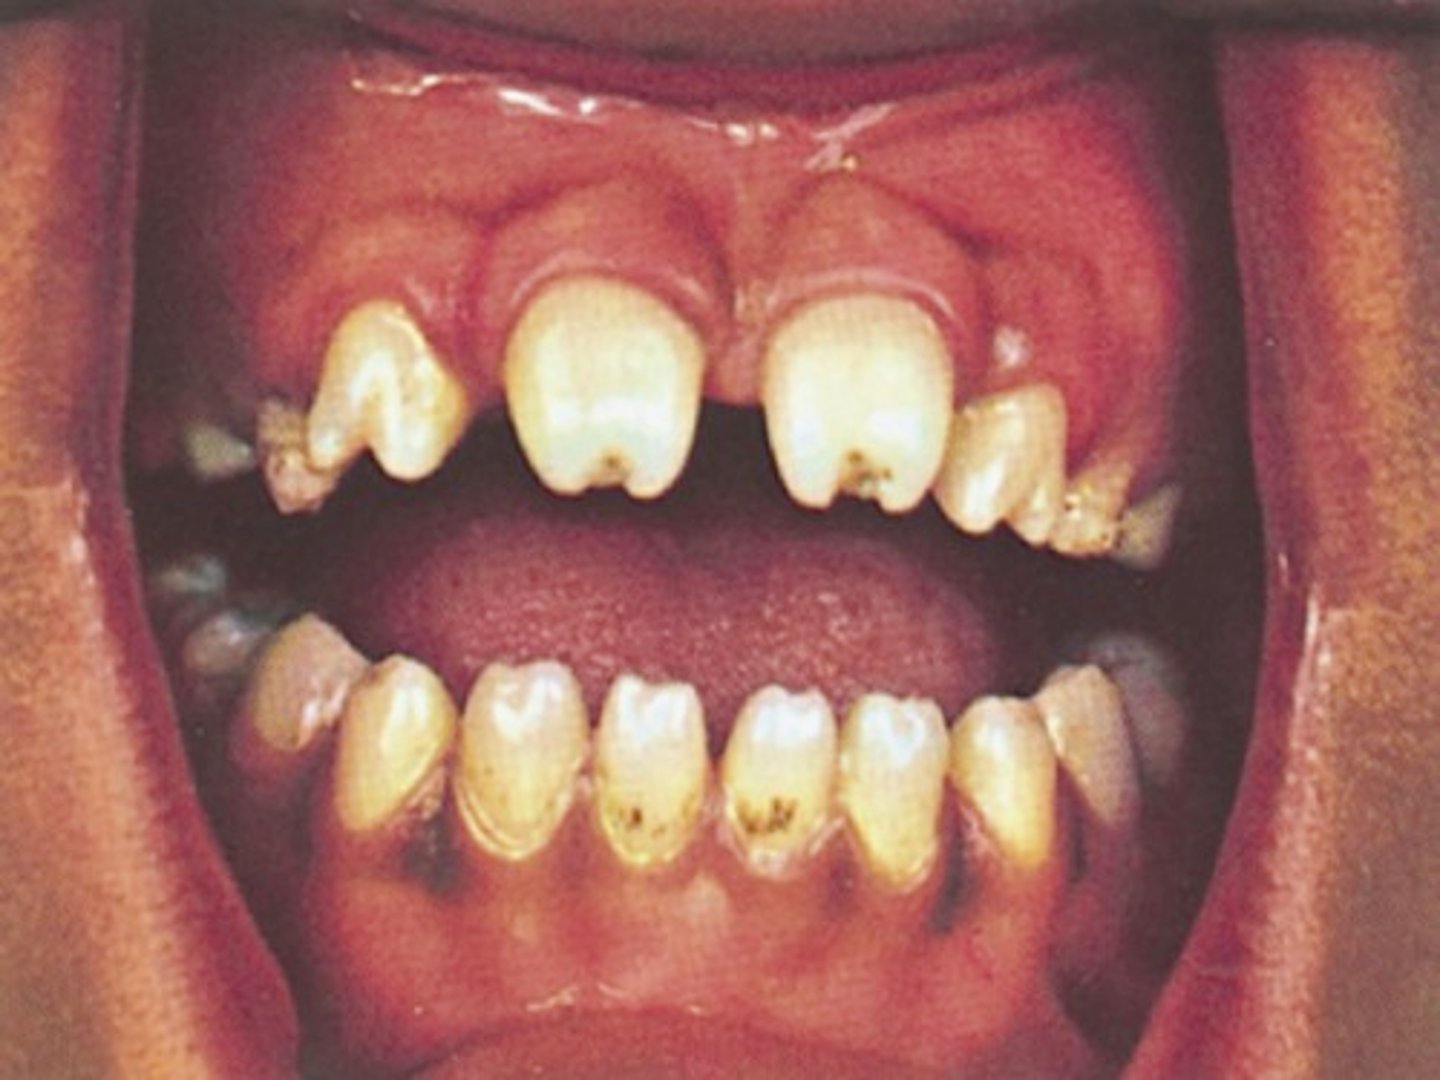

mulberry molars, screwdriver shaped incisors , maxillary anteriors with central depression

syphillis

____ can cause rampant decay due to lack of saliva to buffer acidic PH

xerostomia

____: can cause rampant caries in todder/infant

baby bottle syndrome